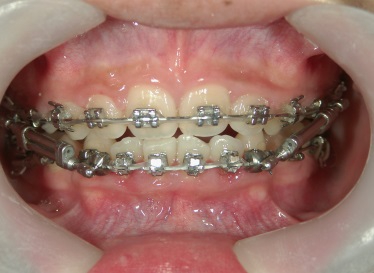

矯正歯科 治療途中 下顎の後退を改善する為、ツインフォースで下顎を前に出す

no.18_2196_治療中_右.jpgno.18_2196_治療中_正面.jpgno.18_2196_治療中_左.jpg